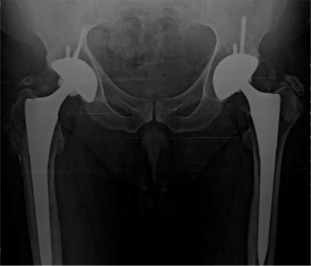

There were 61 patients (50 male, 11 female) with 105 affected hips (72% bilateral, 28% unilateral). The average patient age at surgery was 41.3 ± 10.2 years old. The age of patients at THA was as follows: <30 years for 14 patients (23 hips), 31–50 years for 41 patients (73 hips) and >50 years for 6 patients (9 hips) (Graph 1 ). The younger age at diagnosis (<30 years old) of AS was correlated with younger age at THA (p < 0.05). Bone ankylosis was detected in 37 (35%) and acetabular protrusion was noticed in 18 (17%) hips in pre-operative radiographs (Fig. 1 , Fig. 2 , Fig. 3 ; Fig. 4 ) (Table 1 ). The mean pre-operative flexion contracture was 20.3°±21.8°. In patients without ankylosis, the mean total hip range of motion (ROM) was 67.8°±25.7°.

Fig. 3. Pre-operative x-ray of a patient with protrusio acetabuli. |